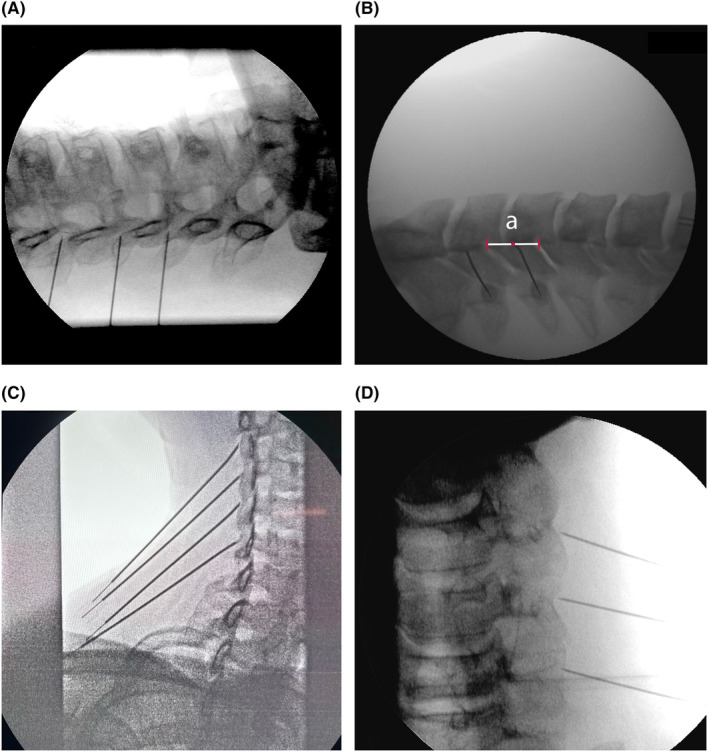

Abstract Image